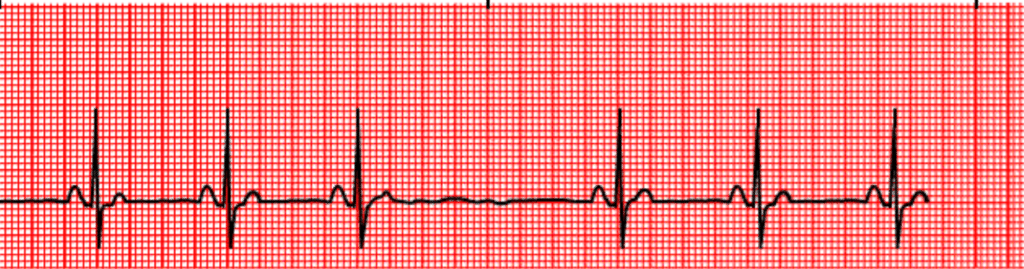

Blok Sinoatrial (SA Blok)

Iramateratur, kecuali pada yang hilang

Frekuensi (HR)biasanya kurang dari 60x/ menit

Gelombang Pnormal, selalu diikuti gelombang QRS

Interval PRnormal

Gelombang QRSnormal

Terdapat episode hilangnya satu atau lebih gelombang P,QRS, T menyebabkan kelipatan jarak antara R – R

SA blok